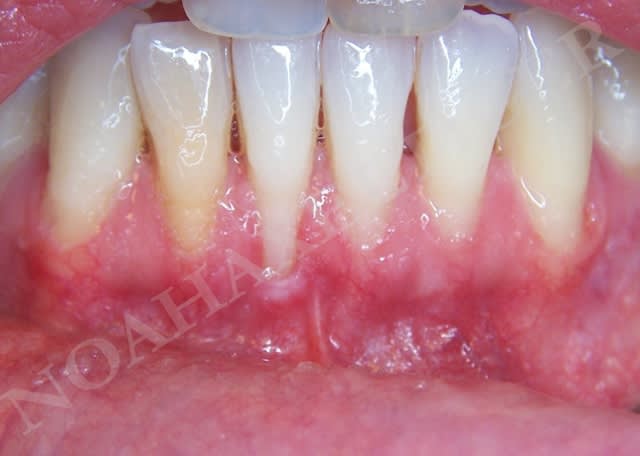

En ce qui concerne la mobilité dentaire, c'est une notion que j'ai appris par le biais du cas suivant :

la patiente présente des rétractions gingivales au niveau du bloc incisivo canin inférieur suite à un traitement parodontal initial. Le problème paro de la patiente est sous contrôle et la patiente désire améliorer l'environnement gingival de 33 à 43.

Très bien madame, on y va :